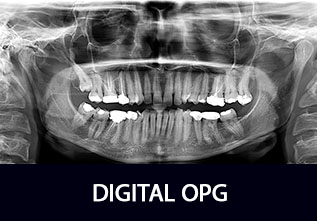

DIGITAL OPG

An OPG (Orthopantomagram) is a panoramic scanning dental X-ray of the upper and lower jaw. It shows a flattened two-dimensional view of a half-circle from ear to ear. Panoramic x-rays allow images of multiple angles to be taken to make up the composite panoramic image, where the maxilla (upper jaw) and mandible (lower jaw) are in the viewed area.

An OPG also demonstrates the number, position and growth of all the teeth including those that have not yet erupted through the gum. It is different from the small close up x-rays dentists take of individual teeth. It shows less fine detail, but a much broader area of view. This can be particularly useful to check hard to see areas like wisdom teeth, or the development of a child’s jaw and teeth, useful for assessing for development generally, but also orthodontic need. It is also often used to check your jaw joint, called the TMJ (temperomandibular joint)